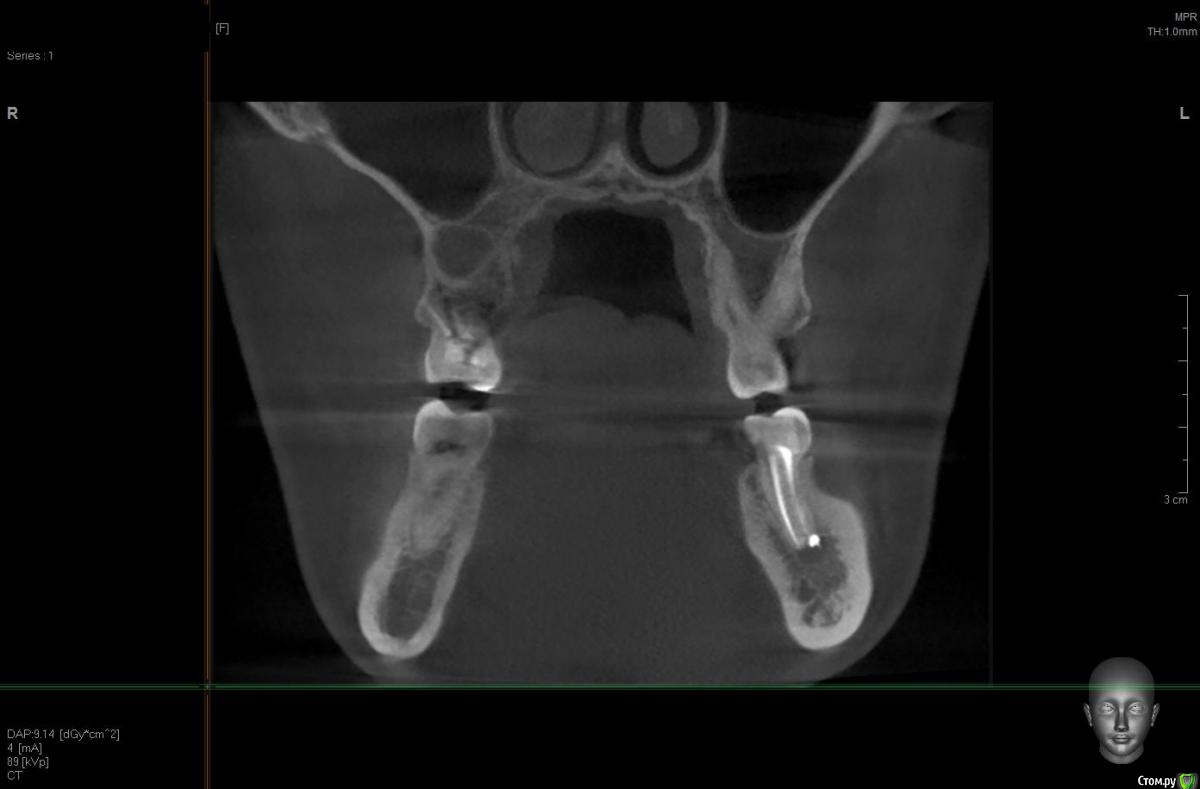

solitary Опубликовано 10 апреля, 2017 Поделиться Опубликовано 10 апреля, 2017 Доброго времени суток! Мое желание исправить прикус превратилось в ходьбу по врачам - от терапевта, до оториноларинголога и хирурга. На ОПТГ (прилагаю) ортодонту не понравилось темное пятно над верхней правой 6-кой. Т.к. хирурга у них в клинике нет, то на консультацию отправили к ортопеду-имплантологу. Предварительный диагноз - киста. Сделали КТ (скриншоты прилагаю).Диагноз подтвердили, но на всякий случай отправили к ЧЛ-хирургу. Тот с КТ от Пикассо не работает (компьютер слабый), но по моим скриншотам также считает, что это киста. Стоматолог врач-терапевт высшей категории вскрыла пломбу и увидела хорошо пролеченные каналы, плюс сделала прицельный снимок 6-ки, который кисту в зоне корня зуба не выявил (даже намека нет). Хотят отправить к оториноларингологу, так как, если верить КТ, киста у границы гайморовой пазухи и консультация ЛОР-врача будет не лишней. Хотелось бы послушать мнение опытных хирургов.-------ОПТГ http://radikal.ru/big/hq2s2k2k9uadn Ссылка на комментарий

Irouil Опубликовано 10 апреля, 2017 Поделиться Опубликовано 10 апреля, 2017 Киста есть. Лор не при чем. Вскрытие пломбы вообще не при чем. Ну а прицельные снимки (после КТ) - ни о чем. 2 Ссылка на комментарий

DmitrySH Опубликовано 10 апреля, 2017 Поделиться Опубликовано 10 апреля, 2017 Скорее всего и лечением можно обойтись. Вполне обычная история. 2 Ссылка на комментарий

колесников Опубликовано 10 апреля, 2017 Поделиться Опубликовано 10 апреля, 2017 Читаю и все больше удивляюсь. Место действия Москва?Удаляйте в плановом порядке,пока дно гайморовой пазухи не вскрыто кистой. В случаях схожих с вашим,рекомендую пациентам совместить удаление с одномоментной имплантацией,пока ещё условия позволяют. 2 Ссылка на комментарий